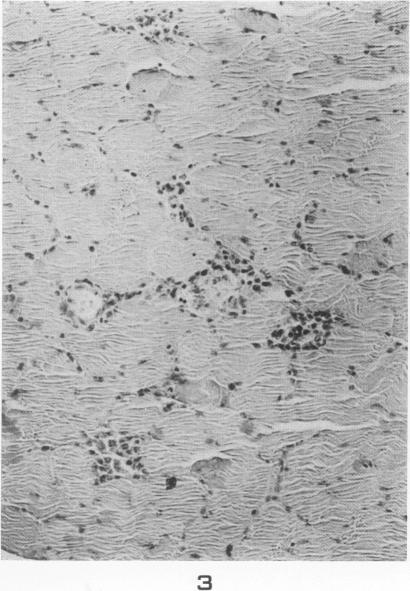

Lesions of skeletal muscle in leptospirosis; review of reports and an experimental study.

Am J Pathol. 1955 May-Jun;31(3):501-19.